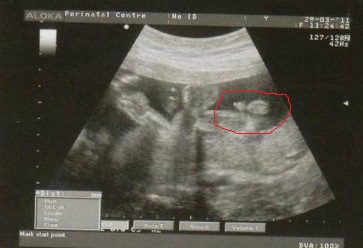

Это фото нашего малыша на 14 неделе.. Тут вроде невооруженным глазом видно.. что за узист такой..

Спасибо огромное за фотку, а то вообще не представляла, каких размеров может быть. В роддоме у новорожденных до колен видела)). У нас не 3д было, снизу смотрели.